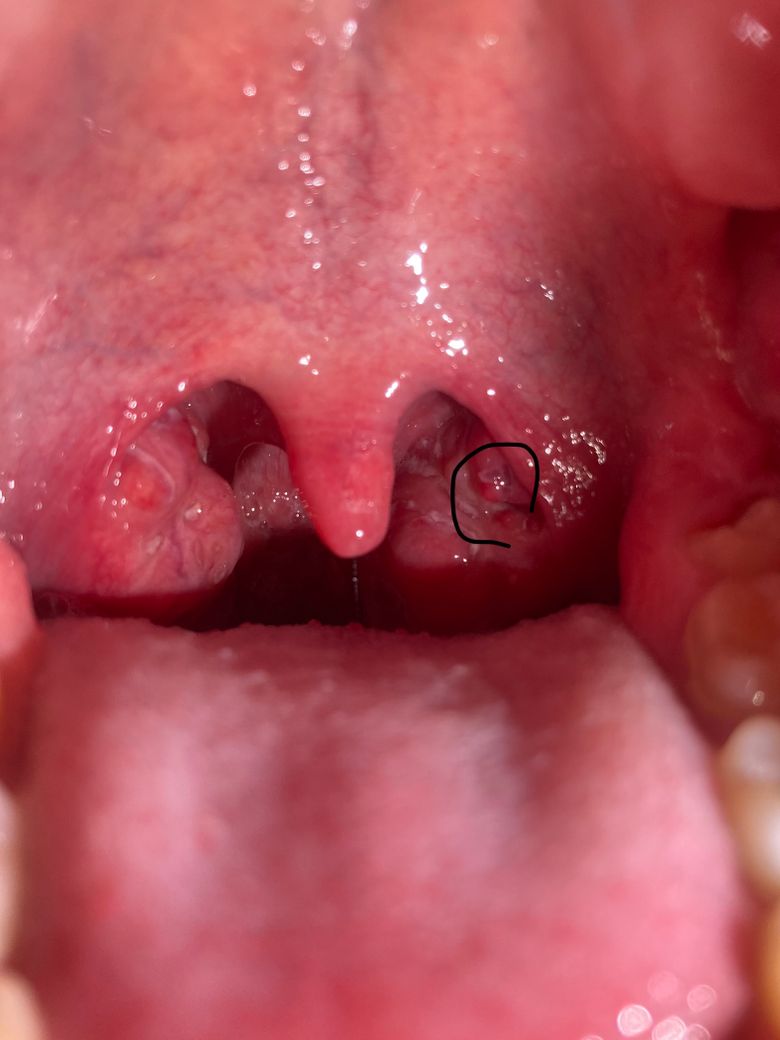

(사진있음)편도쪽에 빨갛게 혹이 났는데 뭔가요?

어제 저녁즈음부터 편도쪽에 빨갛고 투명한 혹이 났습니다 침삼킬때 이물감이 들어 확인해보니 저렇습니다. 추가로 편도 주위에 가래라고 해야할지 모르겠는 흰 이물들도 보입니다.

2년정도 흡연했는데 편도암 같은건 아니겠죠?

직접 진찰이 아니라 제한적이나 올려주신 사진으로 미루 편도가 붓고 염증이 동반된 것으로 생각됩니다.

올려주신 사진으로 보았을때 편도의 크기는 크지만 편도암의 양상으로 보이지는 않습니다.